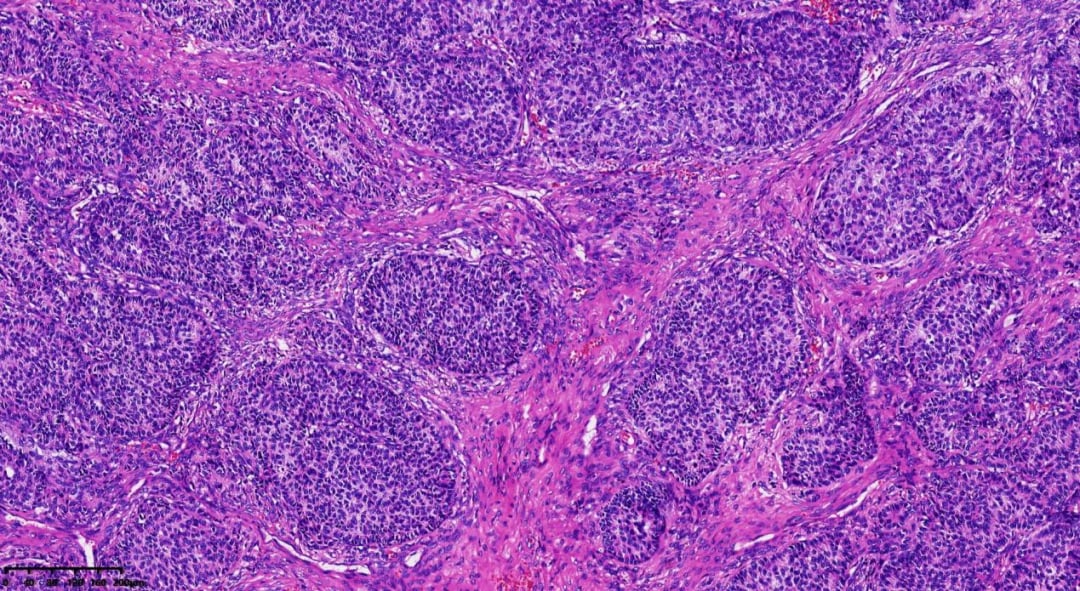

在显微镜下,肿瘤细胞呈现出多种独特的排列模式,为病理诊断提供了关键依据:

肿瘤呈巢状、岛屿状分布,细胞较小

可见间质分隔

- 组织病理学:瘤组织排列模式多样,同一肿瘤内可能出现多种结构,包括弥漫性、结节状、小梁状、条索样、岛屿状、滤泡状、波浪状、脑回样及肉瘤样。少数病例可见囊性变区域,甚至形成假乳头。瘤细胞通常胞质稀少、淡染,大小相对一致,界线不清,呈卵圆形或多边形,细胞核轮廓不规则,可见核沟或呈咖啡豆状。核分裂象通常较少见,75%的病例中每10个高倍视野(HPF)少于3个。

- Call-Exner小体是AGCT的典型特征,表现为瘤细胞围绕中心腔无定向排列,中心腔内含有核碎屑的嗜酸性分泌物或基底膜样粉染物。